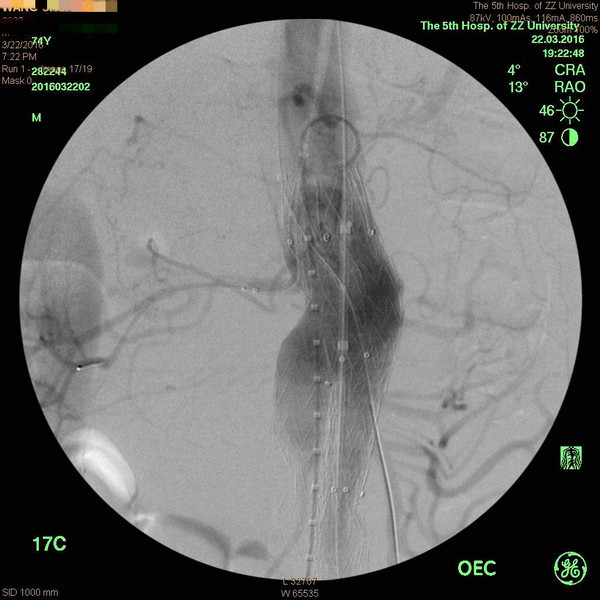

腹主动脉破口较大,周边巨大血肿

可面对患者家属殷切的眼神、王兵教授决定冒着风险为患者手术治疗。考虑到患者破裂腹主动脉瘤病情的复杂性,只有通过腔内技术置入覆膜支架彻底隔绝瘘口,才能有效治疗病变,可却必须封堵肾动脉和肠系膜上动脉。面对这个问题,王兵教授果断提出置入“烟囱”支架,即封堵瘤腔,又保证肾脏及肠道供血。方案制定后,完成术前准备,患者立即送入血管外科复合手术室。王兵教授带领血管外科崔文军副主任、安乾、司江涛等手术组成员当即开展快速而精确的手术。术中造影显示与术前CTA一致,首先经锁骨下动脉置入肾动脉及肠系膜上动脉“烟囱”支架,之后经股动脉引入腹主动脉覆膜支架,通过精确定位后,准确释放支架,之后复查造影显示瘤腔隔绝满意,肾动脉及肠系膜上动脉血流通畅。术后患者逐渐清醒,病情转危为安,维持了生命。血管外科施敏护士长带领的护理组24小时守候,加强术后护理。经过精心的治疗及护理,患者的腹痛等临床症状消失,生命体征平稳,病情大幅好转。